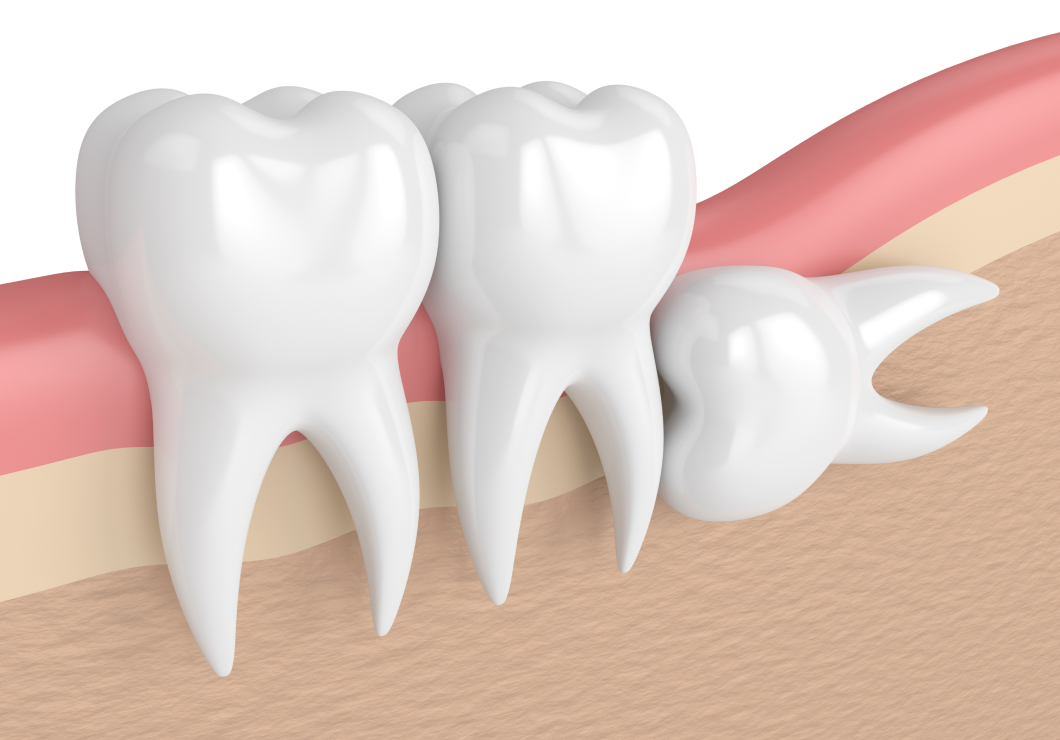

親知らず

親知らずは、永久歯の中でも最後に生えてくる奥歯です。一般的に永久歯は15歳前後で生えそろいますが、親知らずは10代後半から20代前半にかけて生えてくることが多い歯です。

親知らずが横向きや斜めに生えてしまうと、歯と歯の間にすき間ができ、炎症や強い痛み、膿が出ることがあります。症状が悪化する前に、早めの受診をおすすめします。なお、当院での親知らずの抜歯は、外部からお招きする専門性の高い歯科医師が担当いたします。